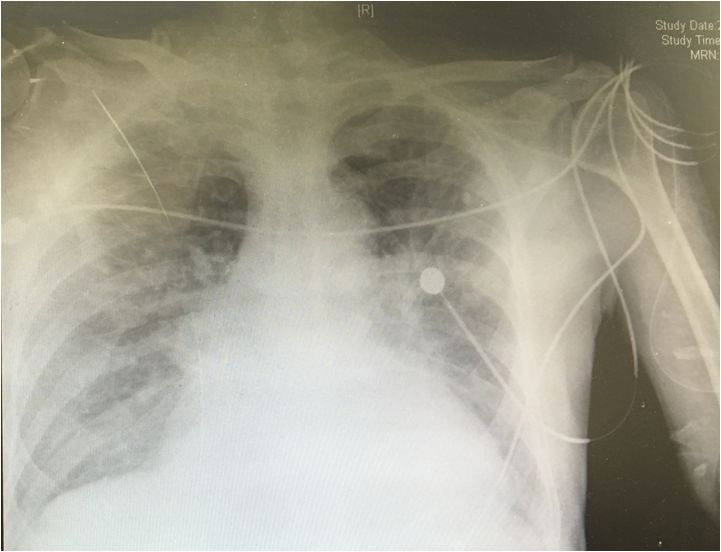

胸片

12.1 两肺淤血重,纹理模糊,左肺上叶结节影,肺动脉段饱满,左心增大。

12.3 肺淤血较前片加重。

12.5 两肺淤血,左肺上叶结节影,主动脉结偏宽,边缘钙化,左心增大。

12.6 肺淤血较前片好转。

12.7 肺淤血较前片加重。

12.9 肺淤血较前好转。

胸片2018-12-01

胸片2018-12-03

胸片2018-12-7